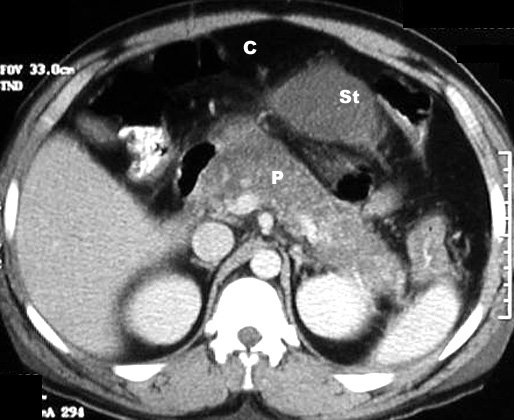

Acute Pancreatitis

CT Findings: Post Contrast

• Diffusely enlarged pancreas with low density from edema

C: Colon

St: Stomach

P: Pancreas